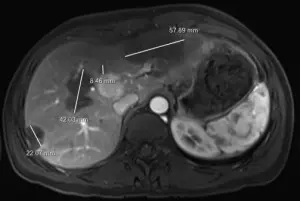

“She had an ultrasound and CT

Waller HEH MRI

scan that showed multiple lesions in her liver,” says Pelletier. “The assumption was that these could be benign lesions; however, after approximately six months, tests showed that the lesions were increasing in size. If they were benign, they would not grow. A biopsy then confirmed the cancer diagnosis.”